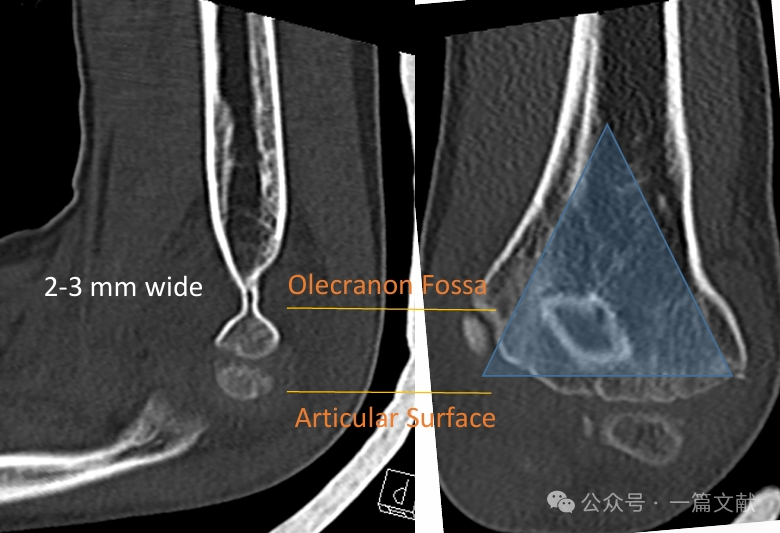

I. Bony Anatomy: The distal humerus is composed of a medial column and a lateral column, which are connected by the articular segment. During fracture, the medial and lateral columns are prone to displacement.

The medial and lateral columns are connected by a thin bone fragment at the olecranon fossa.

* This area represents a structural weak point, making it susceptible to fracture.